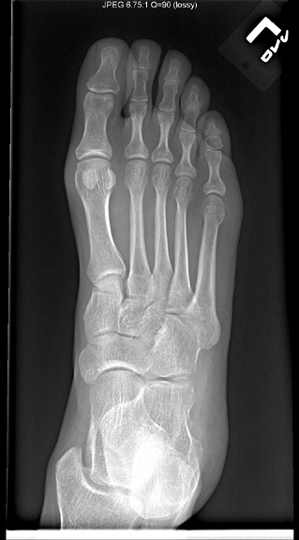

Identify the bones seen. Click the image for labeling.